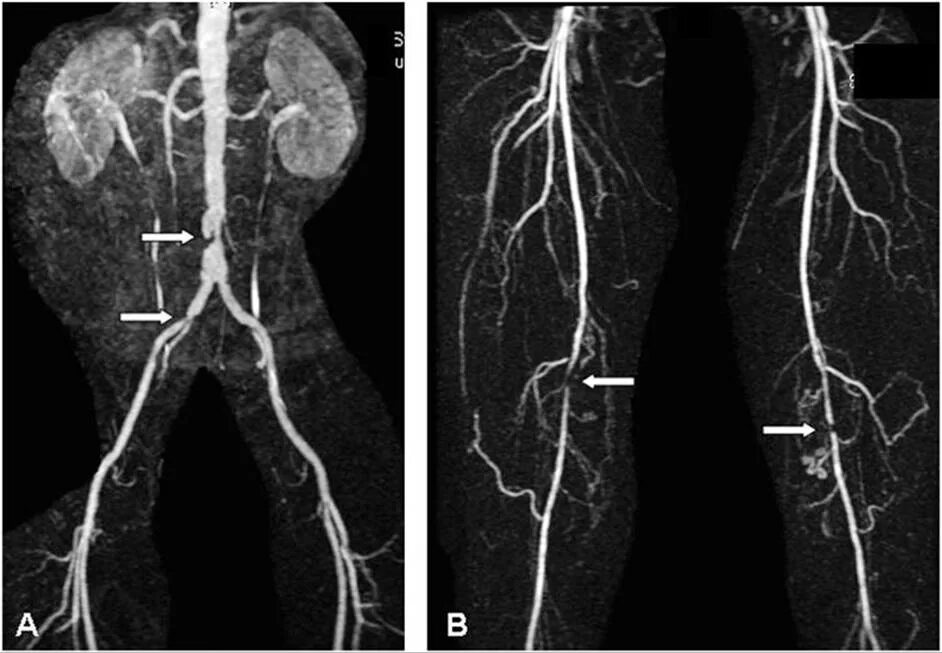

Стенты мрт